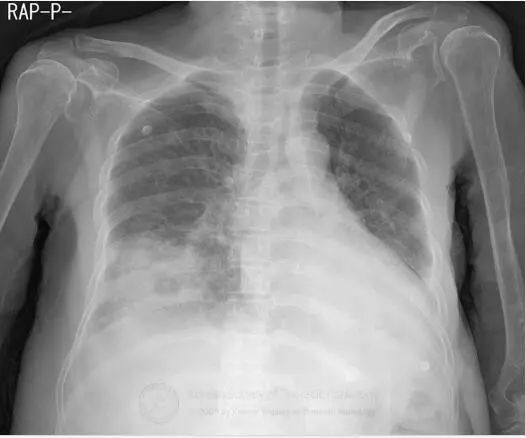

图1胸片示右肺下叶空洞性实变和左肺下叶实变。CT示右肺下叶类圆形实变伴中央磨玻璃影(反晕征),和空洞性病变。可见双侧胸腔积液。

支气管镜活检,真菌菌丝提示毛霉病。

诊断:毛霉病